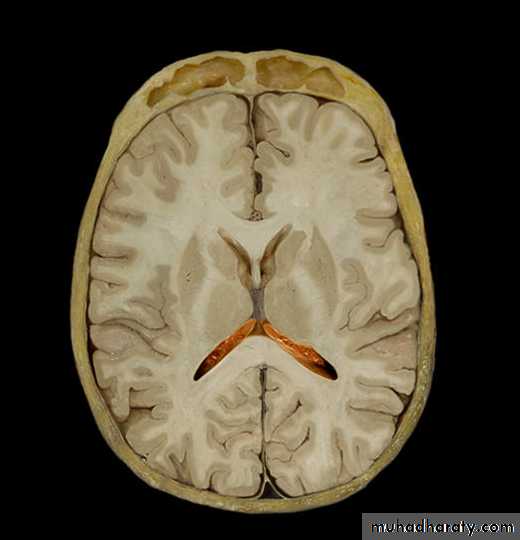

4th Ventricle

It is a cavity of the rhombencephalon• It has a roof and floor.

• The floor is formed by two parts, medullary & pontine part.

• The roof formed by cerebellum

• It has 3 foramina, one is median (foramen of Magendie) located posteriorly and two are lateral (foramina of Lushka)

Ventricles

Lateral

Third

Fourth